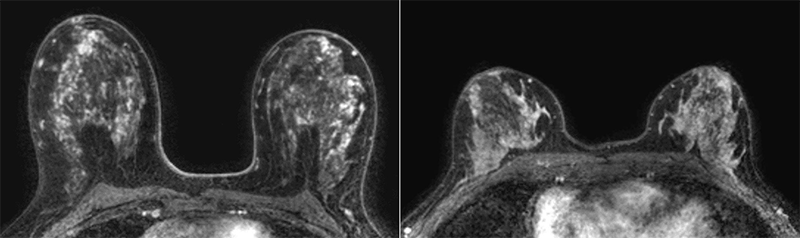

Representative transverse dynamic contrast-enhanced MRI scans in patients in the low and high tertiles of volume of enhancing parenchyma. Please note differences in high and low volumes of enhancing parenchyma are not visible to the naked eye on MRI scans. Left: Baseline MRI scan in a 50-year-old woman with a body mass index (BMI) of 23 and marked background parenchymal enhancement (BPE) who was stratified into the high tertile of volume of enhancing parenchyma. Cancer was detected with MRI in the second screening round. Right: Baseline MRI scan in a 51-year-old woman with a BMI of 24 and marked BPE who was stratified into the low tertile of volume of enhancing parenchyma. No cancer was detected during 6 years of follow-up. https://pubs.rsna.org/doi/10.1148/radiol.222841 © RSNA 2023

After adjusting for age, BMI and BPE, the researchers found that breast cancer occurrence was greater in women with higher volumes of enhancing parenchyma compared to women with low volumes of enhancing parenchyma.